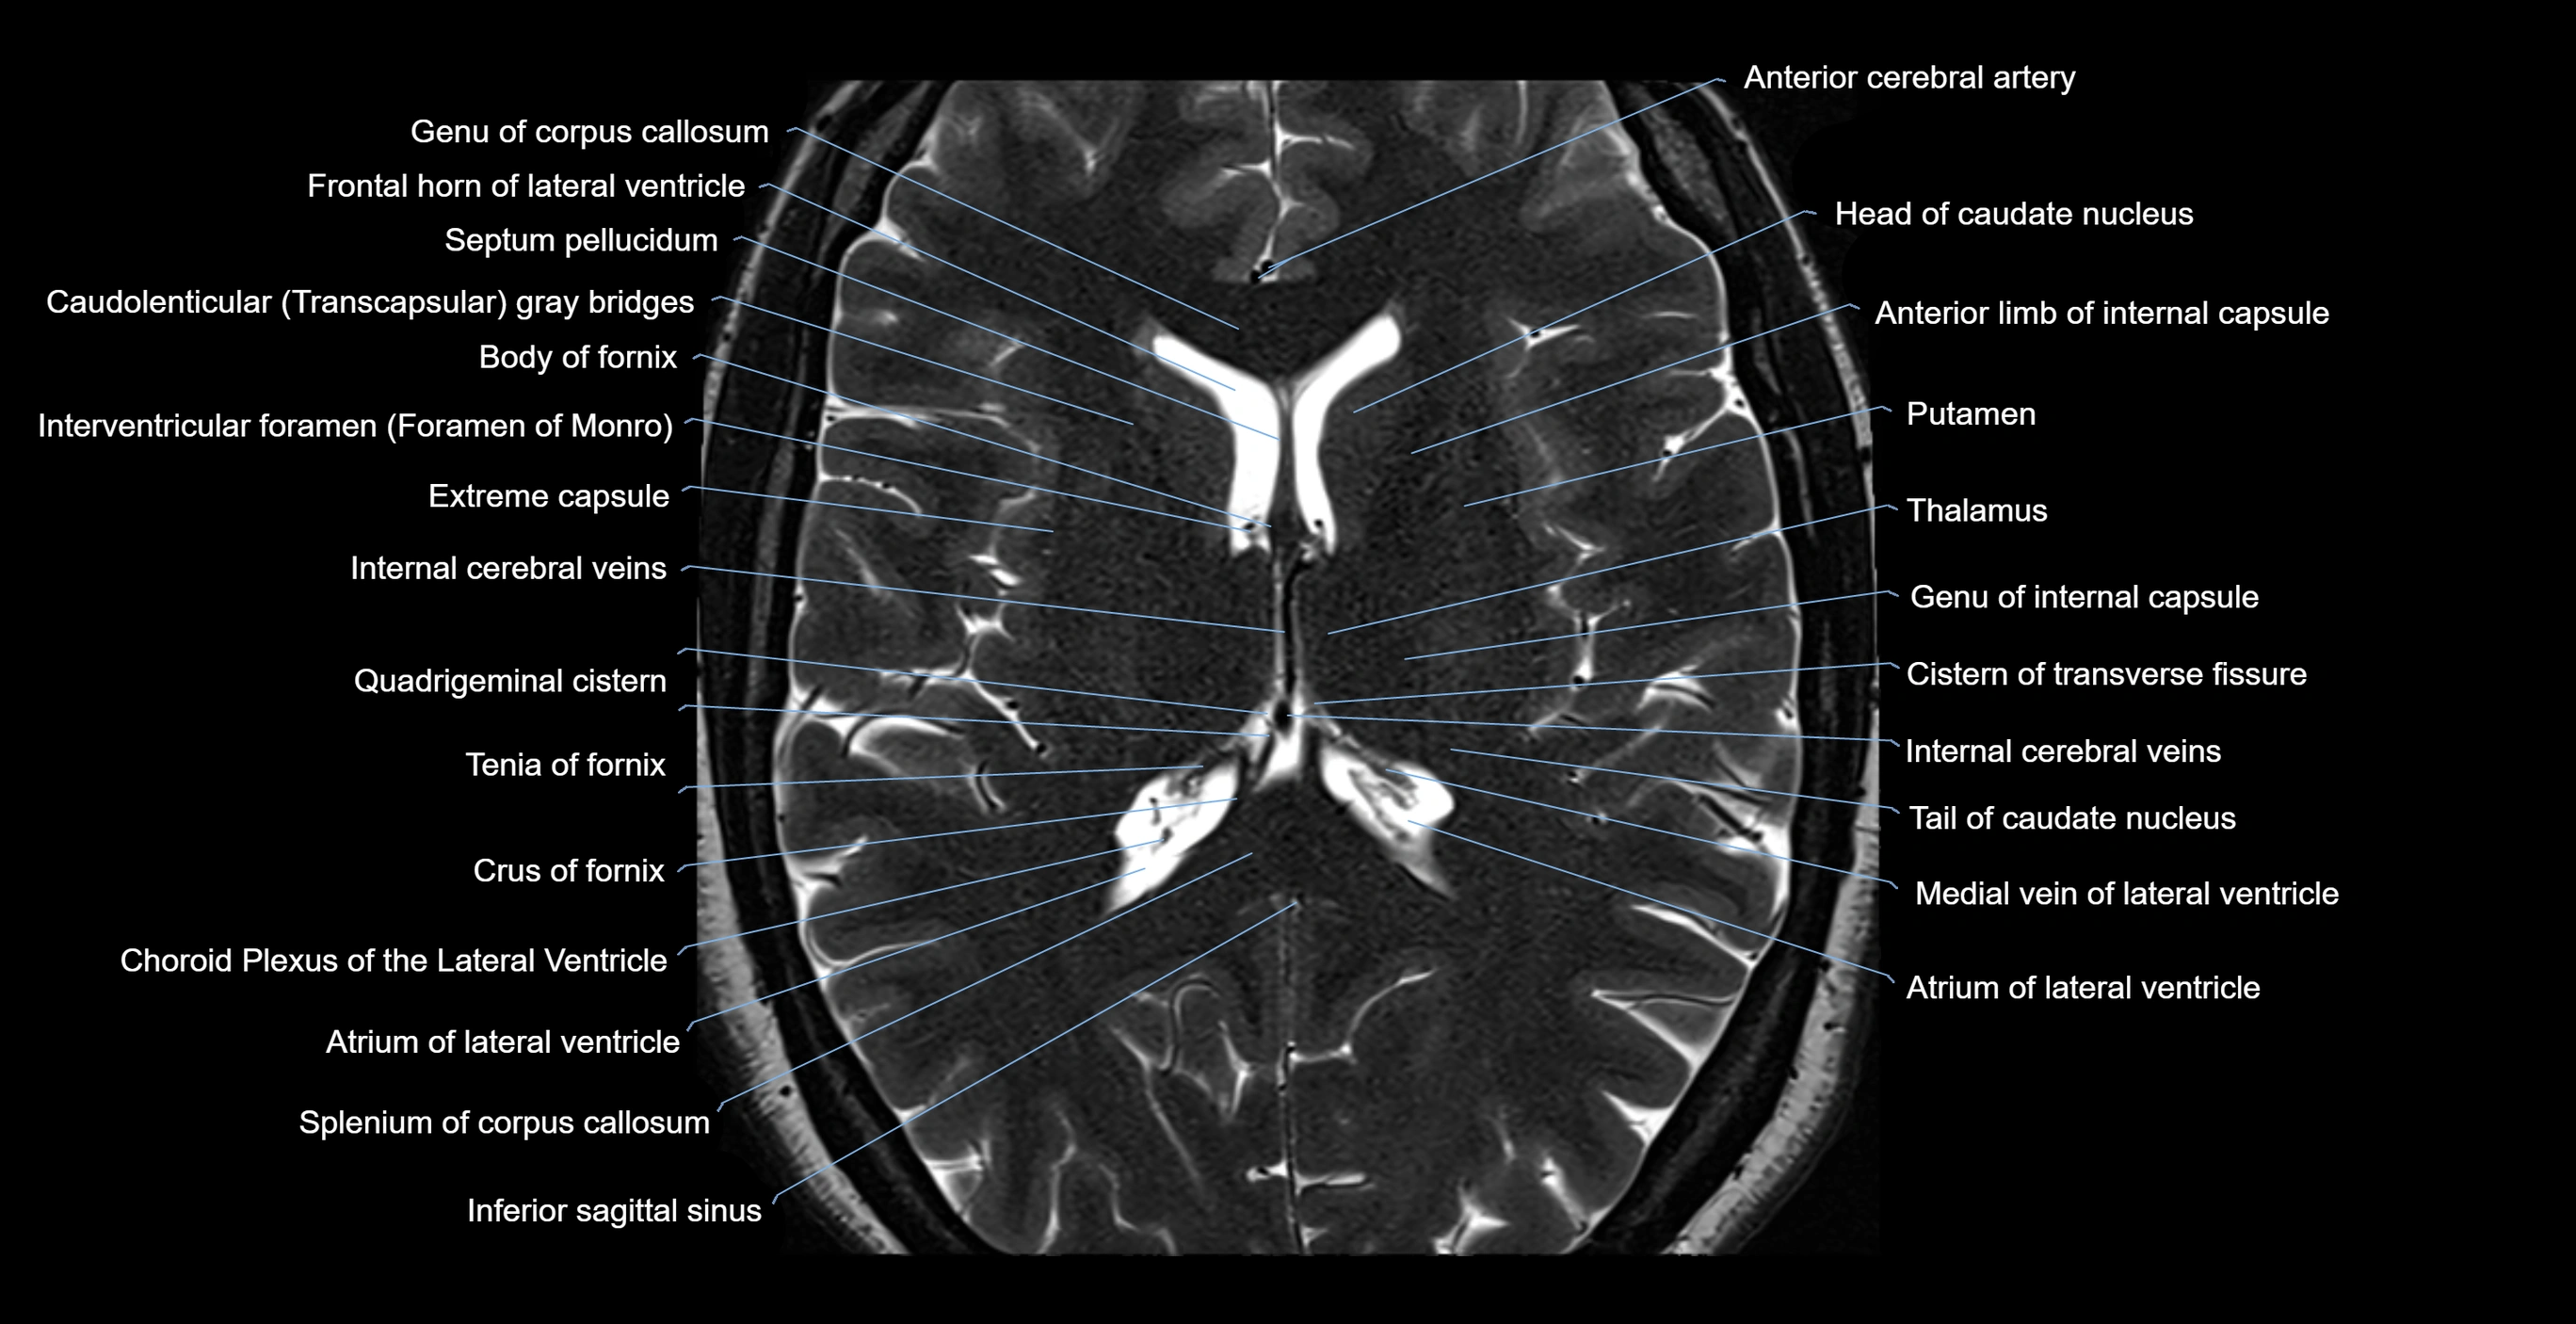

MRI images